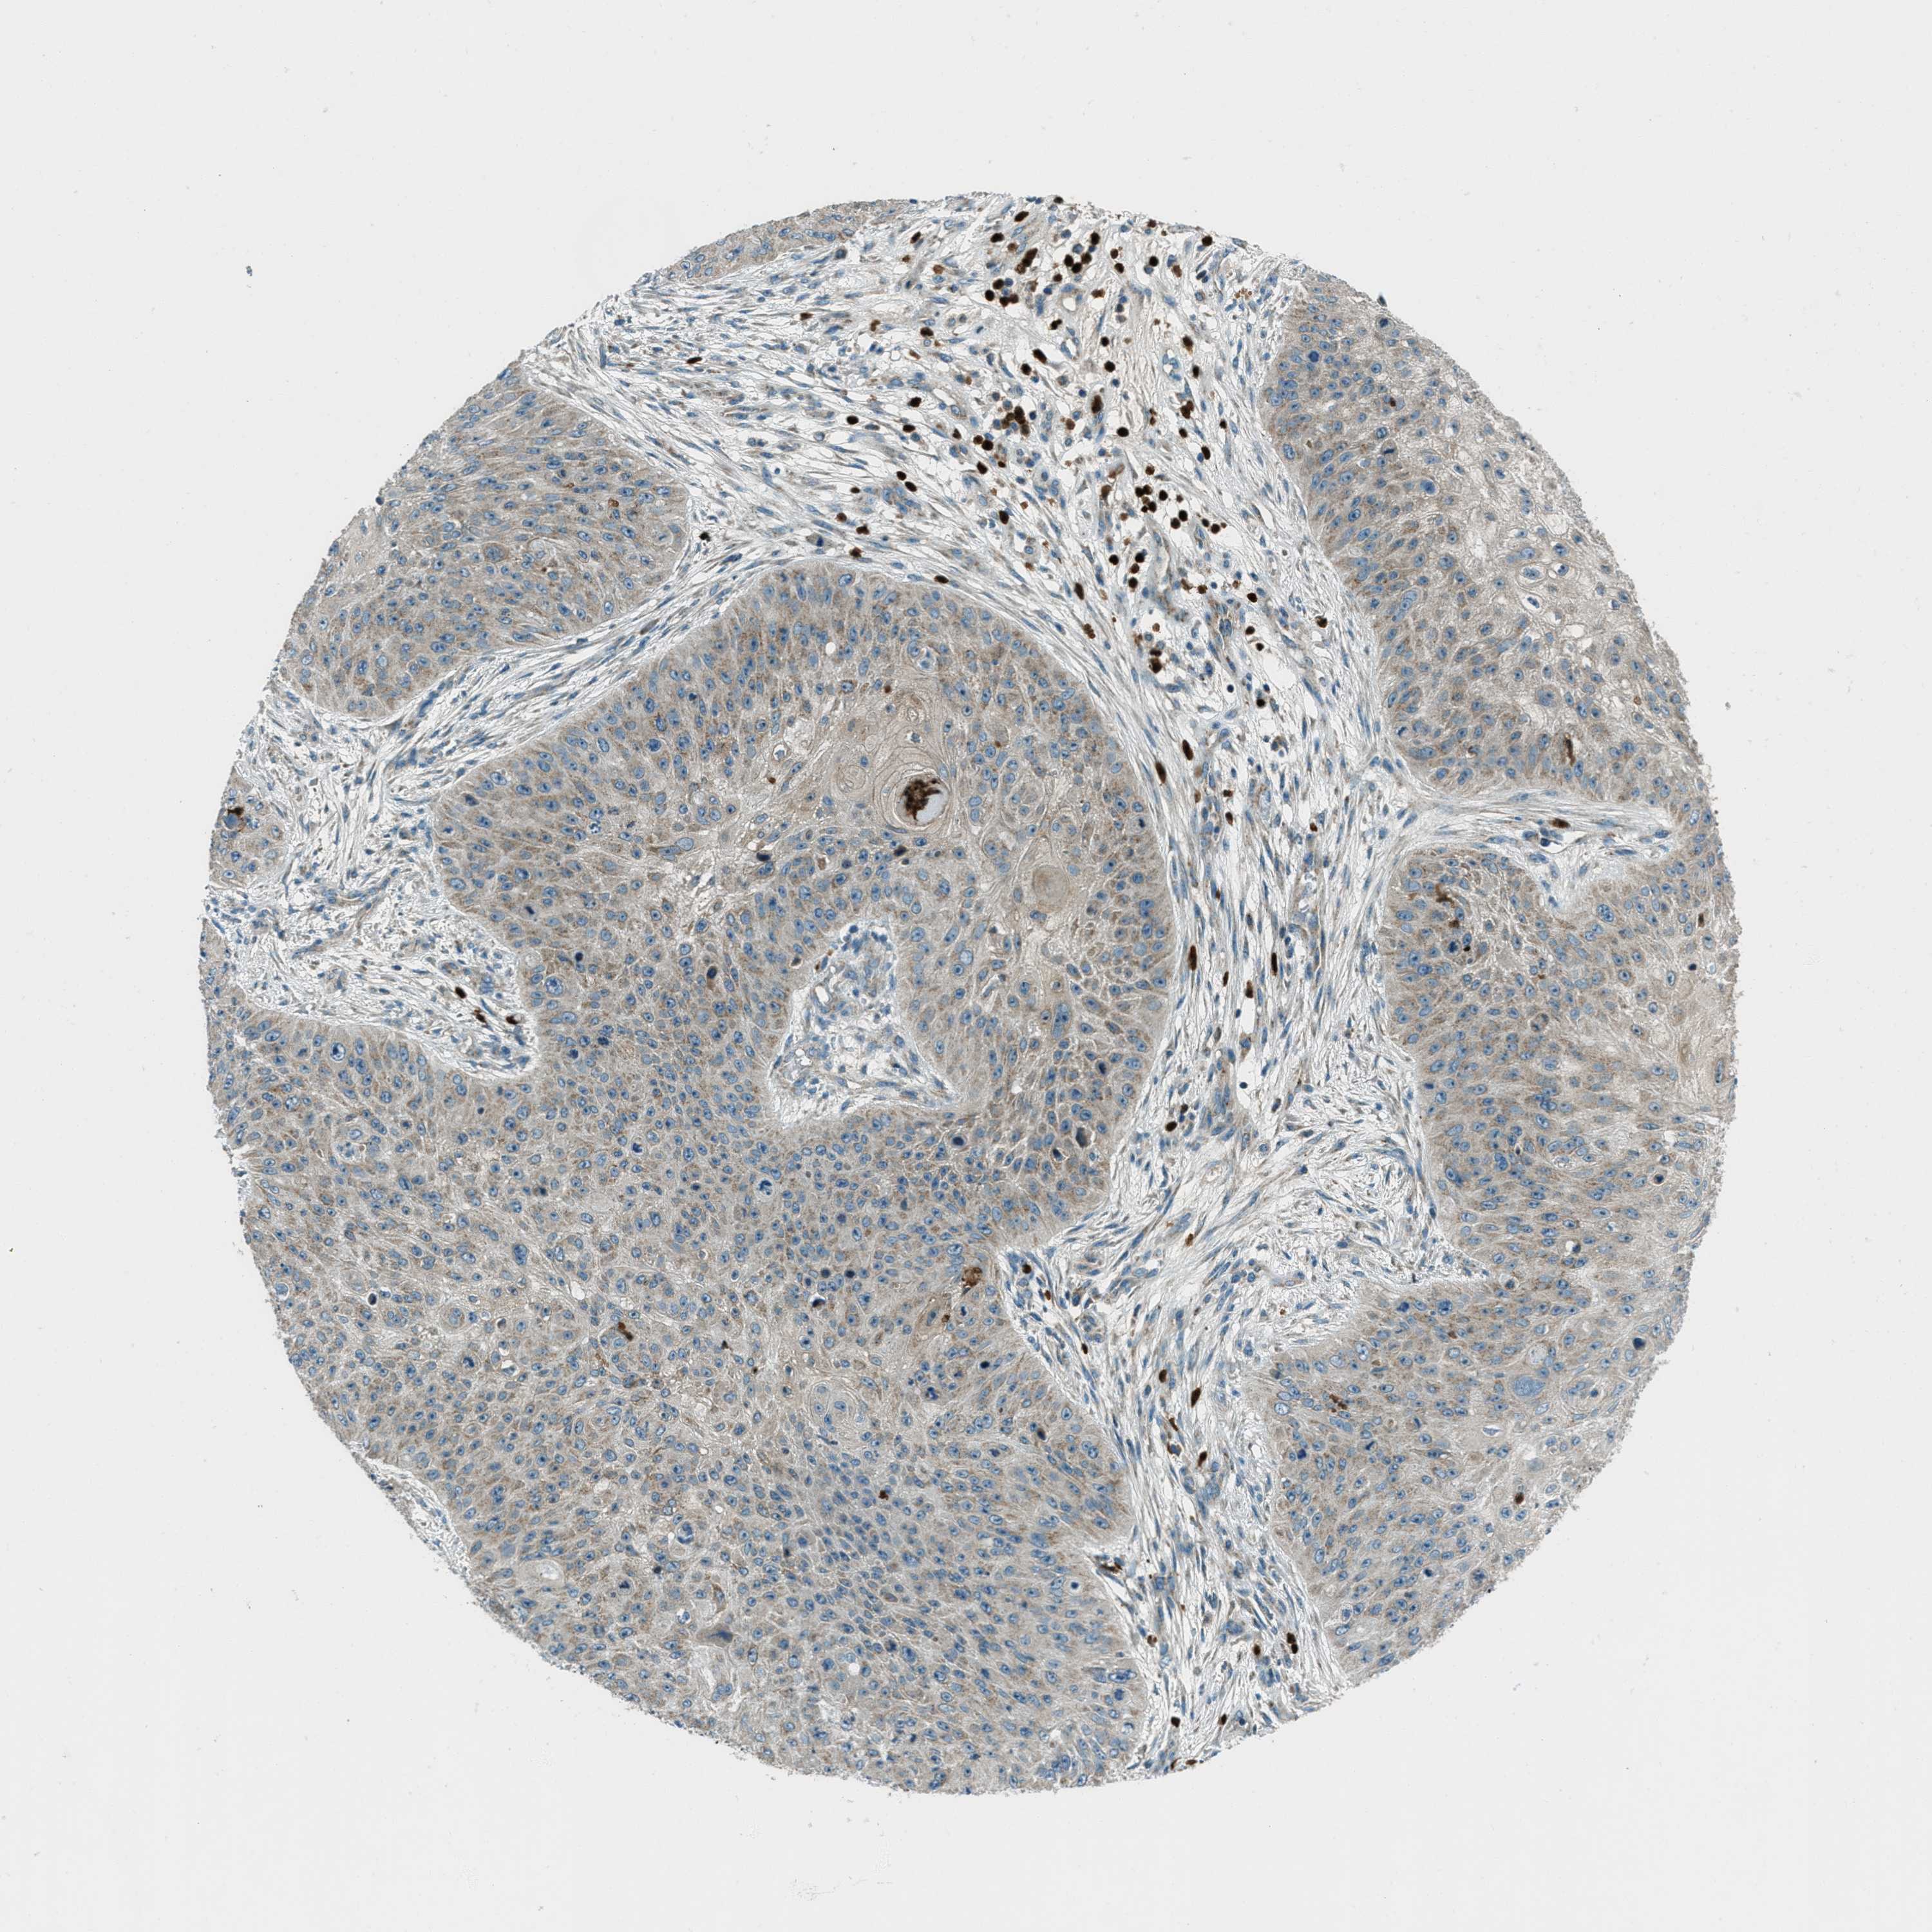

SKIN CANCER - Protein expressioni

A mouse-over function shows sample information and annotation data. Click on an image to view it in a full screen mode. Samples can be filtered based on level of antibody staining by selecting one or several of the following categories: high, medium, low and not detected. The assay and annotation is described here.

Each image is clickable and will lead to virtual microscopy that enables deeper exploration of all samples and also displays staining intensity scores, fraction scores and subcellular localization as well as patient and tissue information for each sample.

Antibody HPA017322

Staining

High

Intensity

Strong

Quantity

>75%

Location

Nuclear

Squamous cell carcinoma in situ, NOS

Squamous cell carcinoma, NOS

Squamous cell carcinoma, metastatic, NOS

Basal cell carcinoma